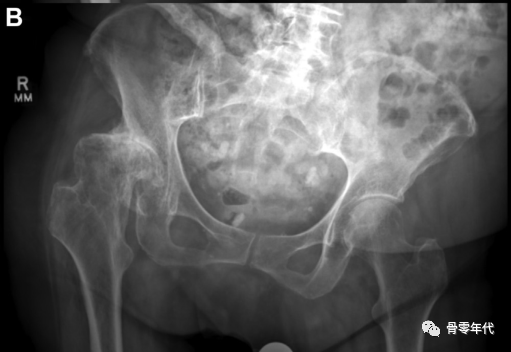

然后画一条水平线连接两个泪滴的最下面的边缘。对于肢体长度,在小转子上选择一个双侧等效的点,并垂直于水平连接(图A)。为了确定偏移量,然后在每个股骨颈上选择一个点,大约在预期的颈部切口水平。从颈部这一点开始画一条线,平行于泪滴间线到坐骨边缘(图B)。

(A)内收和内旋对右髋关节偏移量的影响。与左侧臀部相比,这会产生一种减少偏移量的感觉。(B)骨盆倾斜对肢体长度和偏移量的影响,通过减小髋关节抬高时的偏移量和肢体长度,而对向下旋转的髋关节产生相反的影响。